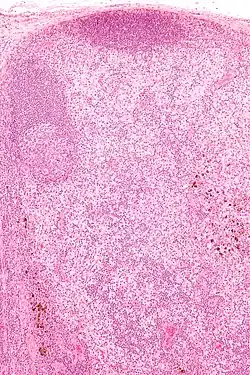

Micrograph showing dermatopathic lymphadenopathy with the characteristic paracortical histiocytosis and melanin-laden macrophages. H&E stain.

Dermatopathic lymphadenopathy is diagnosed by a lymph node biopsy. It has a characteristic pattern of histomorphology and immunohistochemical staining:

• Paracortical histiocytosis

• Melanin-laden macrophages

• Eosinophils

• Plasma cells (medulla of lymph node)